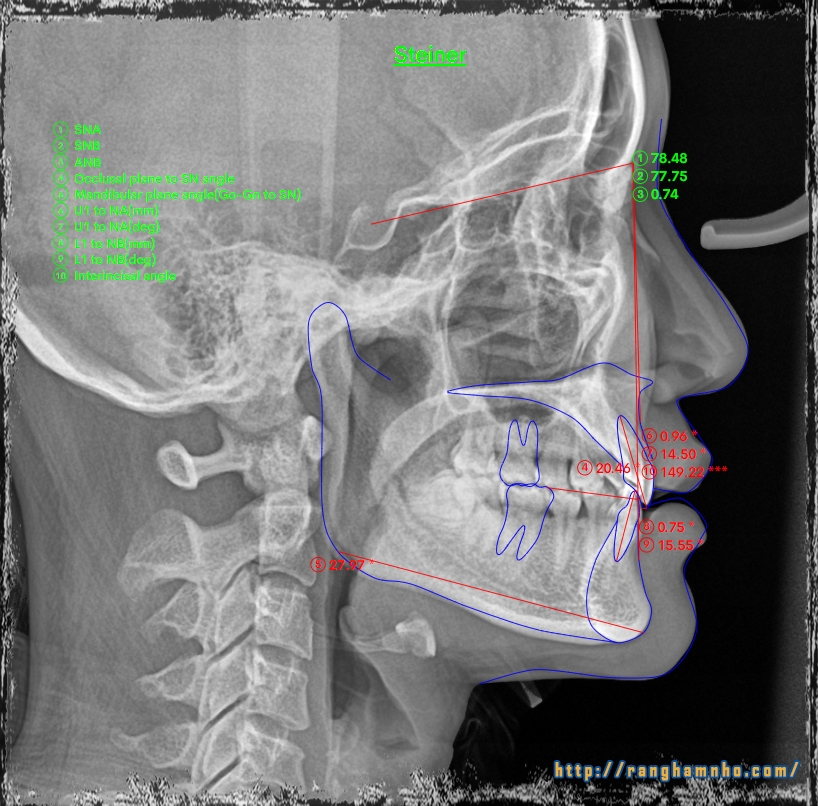

Kết quả phân tích phim mặt nghiêng